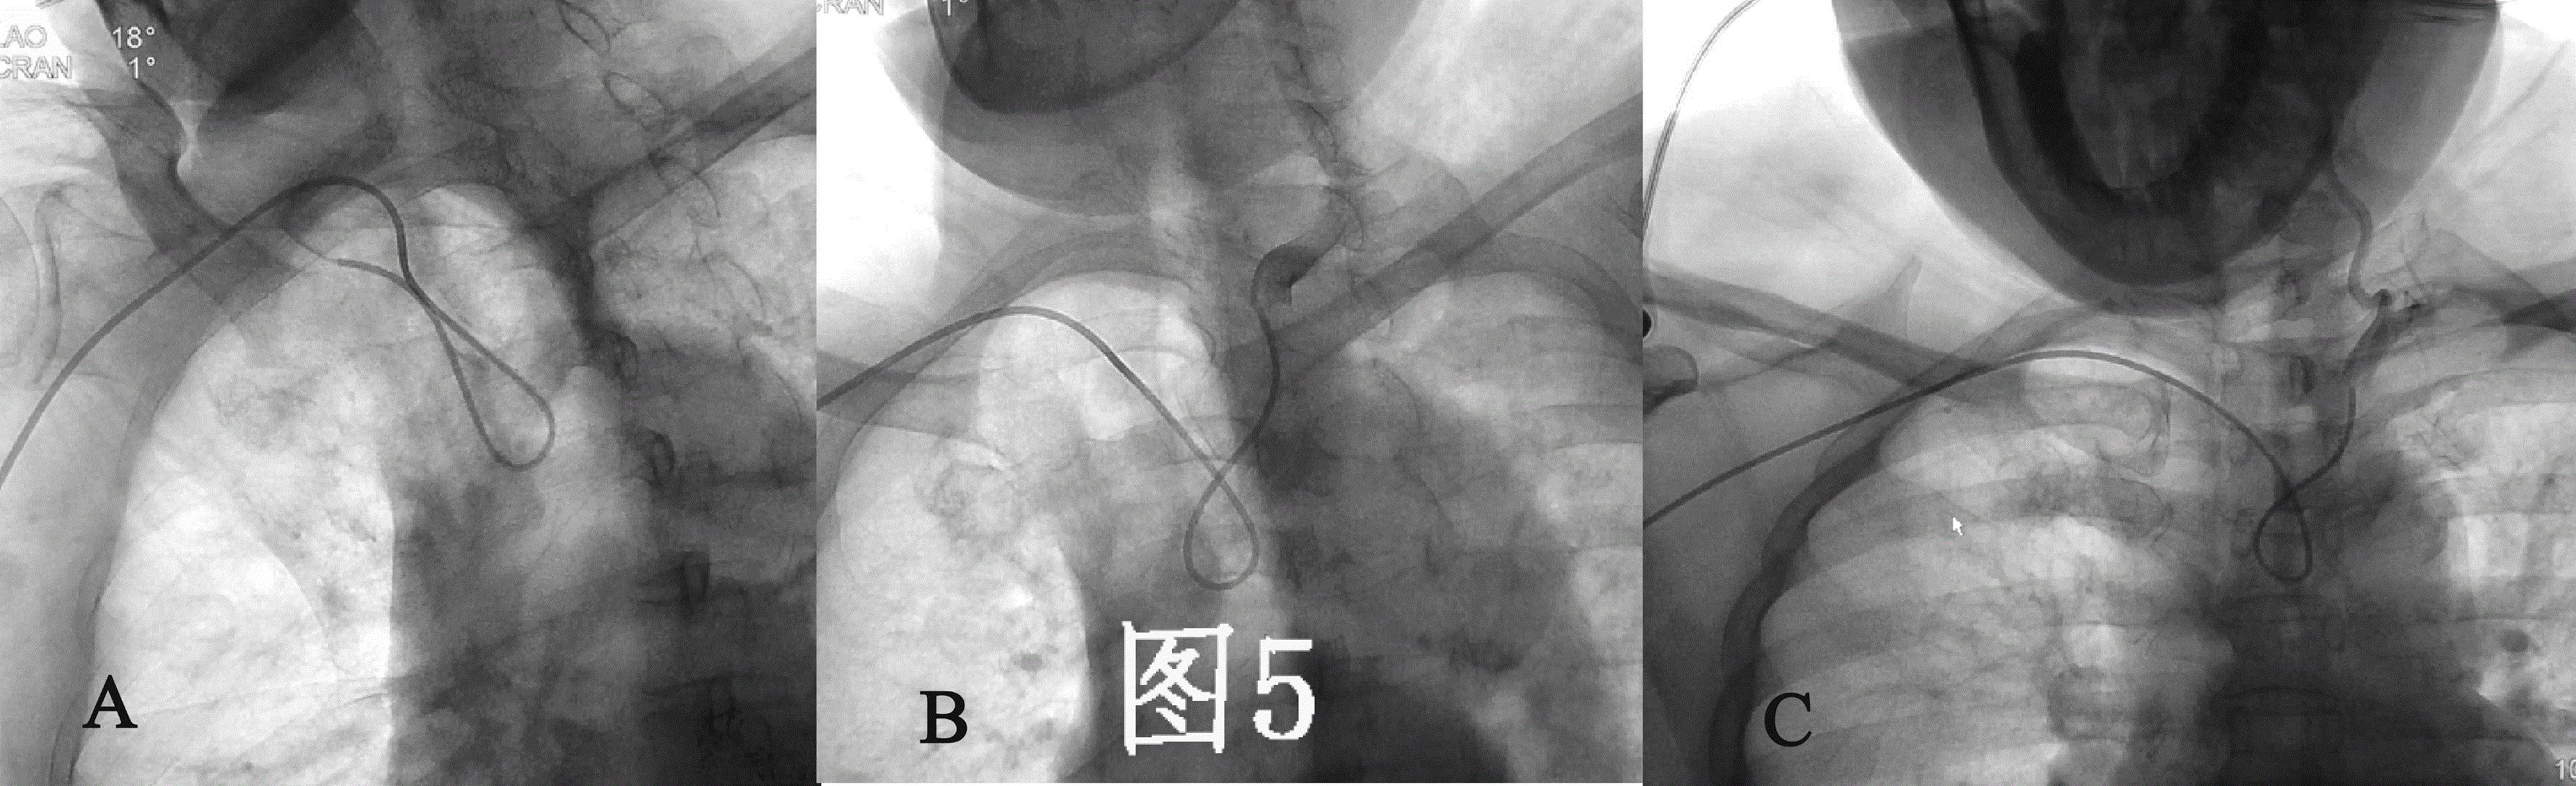

因此, 需使用西蒙管的反勾技术(使导管扭曲呈“8”字形而不是导管原塑性的形状,使得导管末端的方向朝上)才能实现血管的超选(图5),这造成导管的操作困难

理想的导管应该是拥有合适的外形,在操作时能简化操作步骤;具有恰当的尺寸,在狭小的空间内游刃有余。 (图C)

如能设计一种专门针对从桡动脉入路可简单、快捷行脑血管造影用的导管则可有效的解决这一难题。